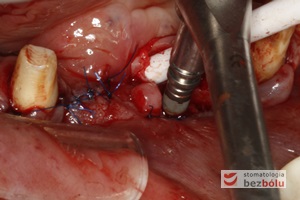

Wprowadzenie implantów - implant Ankylos umożliwia wprowadzenie pod wyrostek co zapewnia wysoką stabilizację

Wprowadzenie implantów – implant Ankylos umożliwia wprowadzenie pod wyrostek co zapewnia wysoką stabilizację

Implanty in situ - wprowadzone podwyrostkowo implanty i wyrostek zębodołowy przygotowany do augmentacji

Implanty in situ – wprowadzone podwyrostkowo implanty i wyrostek zębodołowy przygotowany do augmentacji